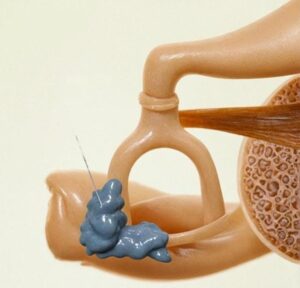

At Richardsons Face Hospitals, we offer the best ENT treatment in India as it is the surgery that is done to treat hearing loss or hearing impairment by removing a dysfunctional small piece of bone known as the stapes, aka stirrup, and replacing the bone with a small piston in the ear. This condition is known as otosclerosis, in which there is abnormal bone remodeling that causes the stapes bone to become unable to vibrate normally, and in turn impairing hearing. This occurs because the stapes bone becomes abnormally fused to the surrounding structures and hinders its vibration. For the best ENT treatment in India, this surgery provides a permanent solution to restore hearing and improve quality of life.

The surgery involves removing the abnormal, dysfunctional bone and replacing it with a small prosthesis made up of Teflon, nitinol, or titanium (varies from patient to patient and availability). When you get the best ENT treatment in India from us, we assure you the permanent cure. This piston now acts in the place of the stirrup and vibrates, permitting sound waves to reach the inner ear and restore hearing. For the Best ENT Treatment in India, this surgery is a highly effective and permanent solution.